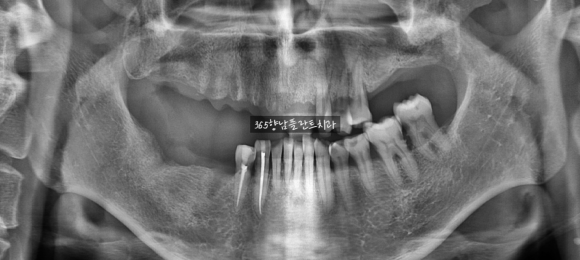

<의식하진정요법을 통해 2번의 수술로 진행한 사례>

수술 전

위 / 아래 2회 의식하진정요법으로 시술